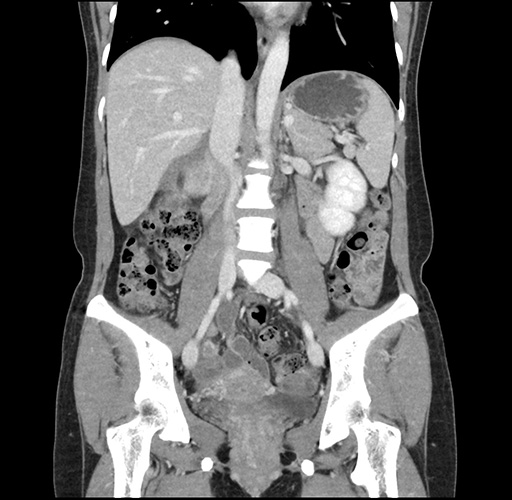

Imaging Analysis

Look through the patient's CT scan to identify any areas of concern for the necessary procedure.

Based on your CT findings, which issue(s) would give reason for "planned slowing down moment(s)" in this case?

Considering a standard left lateral sectionectomy procedure, what step(s) of the operation would you do differently in this case ?